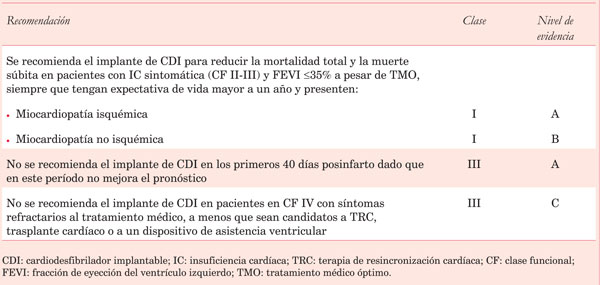

Las arritmias ventriculares malignas son la causa de la gran mayoría de estas MS. Numerosos ensayos clínicos randomizados, que se comentarán más adelante, han demostrado que el CDI es la terapéutica más eficaz para reducir la MS dado que es capaz de detectar y terminar con las arritmias ventriculares. Inicialmente se estableció su beneficio, en términos de sobrevida, para pacientes que experimentaron y sobrevivieron a una arritmia ventricular sintomática o a un paro cardiorrespiratorio (prevención secundaria)2), (3), (4. En los últimos 15 años se ha demostrado, además, que este beneficio se extiende a la prevención primaria, es decir, a tratar el primer evento potencialmente fatal (Figura 1). Numerosos estudios avalan la indicación de implante profiláctico de CDI para subgrupos de alto riesgo de presentar arritmias ventriculares malignas. Es muy importante estratificar correctamente el riesgo y sopesarlo con el de infección, choques inapropiados, calidad de vida, mortalidad asociada al dispositivo, así como también costos y comorbilidades para poder determinar la población en que el implante de CDI tendrá impacto en la disminución de la mortalidad total y no solo arrítmica. El mayor conocimiento de la historia natural de la enfermedad, de sus mecanismos fisiopatológicos, así como de los resultados de estudios recientemente publicados determinan que sea necesario analizar por separado el rol del CDI en prevención primaria en la cardiomiopatía isquémica (CMI) y en la cardiomiopatía no isquémica (CMNI).

Figura 1: Hazard ratios (HR) para mortalidad total: cardiodesfibrilador implantable versus tratamiento convencional en los principales estudios de prevención primaria en cardiomiopatía isquémica y no isquémica. Modificado de referencia 5.

En suma, existe evidencia contundente derivada de estudios de grandes dimensiones que sustentan la indicación clase I del implante profiláctico de CDI en pacientes con CMI luego de la fase aguda posinfarto, estratificados básicamente por la FEVI y la clase funcional (FEVI 35% y CF II-III (Tabla 1)13.

2.2. CDI en la prevención primaria de muerte súbita en cardiomiopatía no isquémica

En contraste con la extensa evidencia que se ha presentado para la CMI, la evidencia para la CMNI es menos robusta. Las guías actuales (Tabla 1) recomiendan el implante de CDI en cierto grupo de pacientes con CMNI, basadas en un metaanálisis publicado en 2004 que reúne los resultados positivos derivados de los estudios SCD-HeFTl (cuyos datos fueron presentados en sesión científica de marzo de 2004, previo a su publicación)10 y del COMPANION14, y los negativos derivados de los estudios CAT15, AMIOVIRIT16 y DEFINITE17. El metaanálisis muestra una reducción de 31% de la mortalidad con CDI vesus tratamiento convencional18.

Dado el impacto potencial que puede tener el resultado negativo del DANISH, se han realizado nuevamente varios metaanálisis que evalúan el efecto del CDI en prevención primaria en estos pacientes, con la inclusión de los estudios clásicos y también de este último. Todos muestran un beneficio en mortalidad total estadísticamente significativo del CDI versus tratamiento médico óptimo, pero no así en pacientes a quienes se les asoció TRC20), (21) .

Si bien hoy día el implante de CDI en prevención primaria continúa siendo una indicación clase I en las guías para pacientes con CMNI, FEVI ?35% y CF II-III (Tabla 1), es probable que a la luz de los últimos estudios analizados se reduzca la indicación en esta subpoblación.